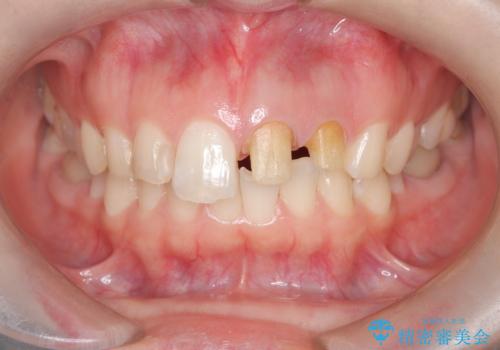

「数日前から前歯に痛みがある」「左上1、2番の色が気になる」

左上1番および2番は失活歯であり、両歯ともに失活に伴う変色を認めました。左上2番に関しては根尖部に透過像を認め、根尖性歯周炎と診断しました。これが前歯部の痛みの原因と考えられました。

治療内容:

左上2番に対して精密根管治療を実施し、感染源の除去を行いました。その後、左上1、2番ともにオールセラミッククラウンによる補綴を行い、審美的な修復を行いました。